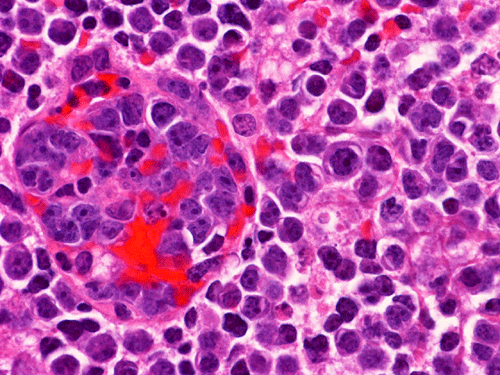

The material for permanent sections is largely semi-liquid in consistency. There are only very few fragments of cerebellar tissue that are infiltrated by the tumor. The bulk of the diagnostic material are solid sheets of neoplastic cells (Panel G). The cytologic features are similar to what we have observed in the cytologic preparation  (Panel H). In essence, the tumor is composed of solid sheets of large polygonal and rather monotonous atypical cells with a thin rim of cytoplasm and molding which lead to a mosaic pattern. These features are consistent with lymphoma. On immunohistochemistry, practically all the neoplastic cells are positive for leukocyte common antigen (LCA) (Panel I), CD20 (Panel J) and many of them are positive for CD79a (Panel K). Only reactive T-cells but not the large, atypical cells are positive for CD3 (Panel L). The neoplastic cells are essentially negative for Bcl-6 (Panel M) but some of them are positive for Bcl-2 (Panel N). The large atypical cells are negative for kappa and lambda light chains on immunohistochemistry. There is no immunoreactivity in the neoplastic cells for cytokeratin (AE1/AE3), S100, pan-melanoma marker (Mart-1, tryptase, and HMB-45).

Similar to the systemic counterparts, diffuse large-B cell lymphomas of the CNS are characterized by large, pleomorphic lympyoid cells. Histologically, however, PCNSL shows the unique angiocentric infiltrating pattern, which is more prominent at the edge of the lesion. The tumor cells dissect and expand the perivascular network in a concentric manner which is best demonstrated by reticulin stain

[click here to see a picture]. Systemic DLBCL does not show this particular pattern of growth. The tumor infiltrates the brain parenchyma between blood vessels as small clusters and individual cells. Confluent areas of tumor may show necrosis, with residual viable tumor cells being found mostly around blood vessels. The boundary of the tumor may be relatively discrete, but it is more common for perivascular cuffs and single infiltrating lymphoma cells to be found at some distance from the tumor mass, extending far away from radiographically evident tumor margins. The malignant lymphocytes lack a cohesive appearance, do not form glands or other structures. The nuclei vary from round to indented or cleaved, and prominent nucleoli can be noted. The cells have only a small amount of basophilic cytoplasm. Variable numbers of mitotic figures and apoptotic cells are seen.